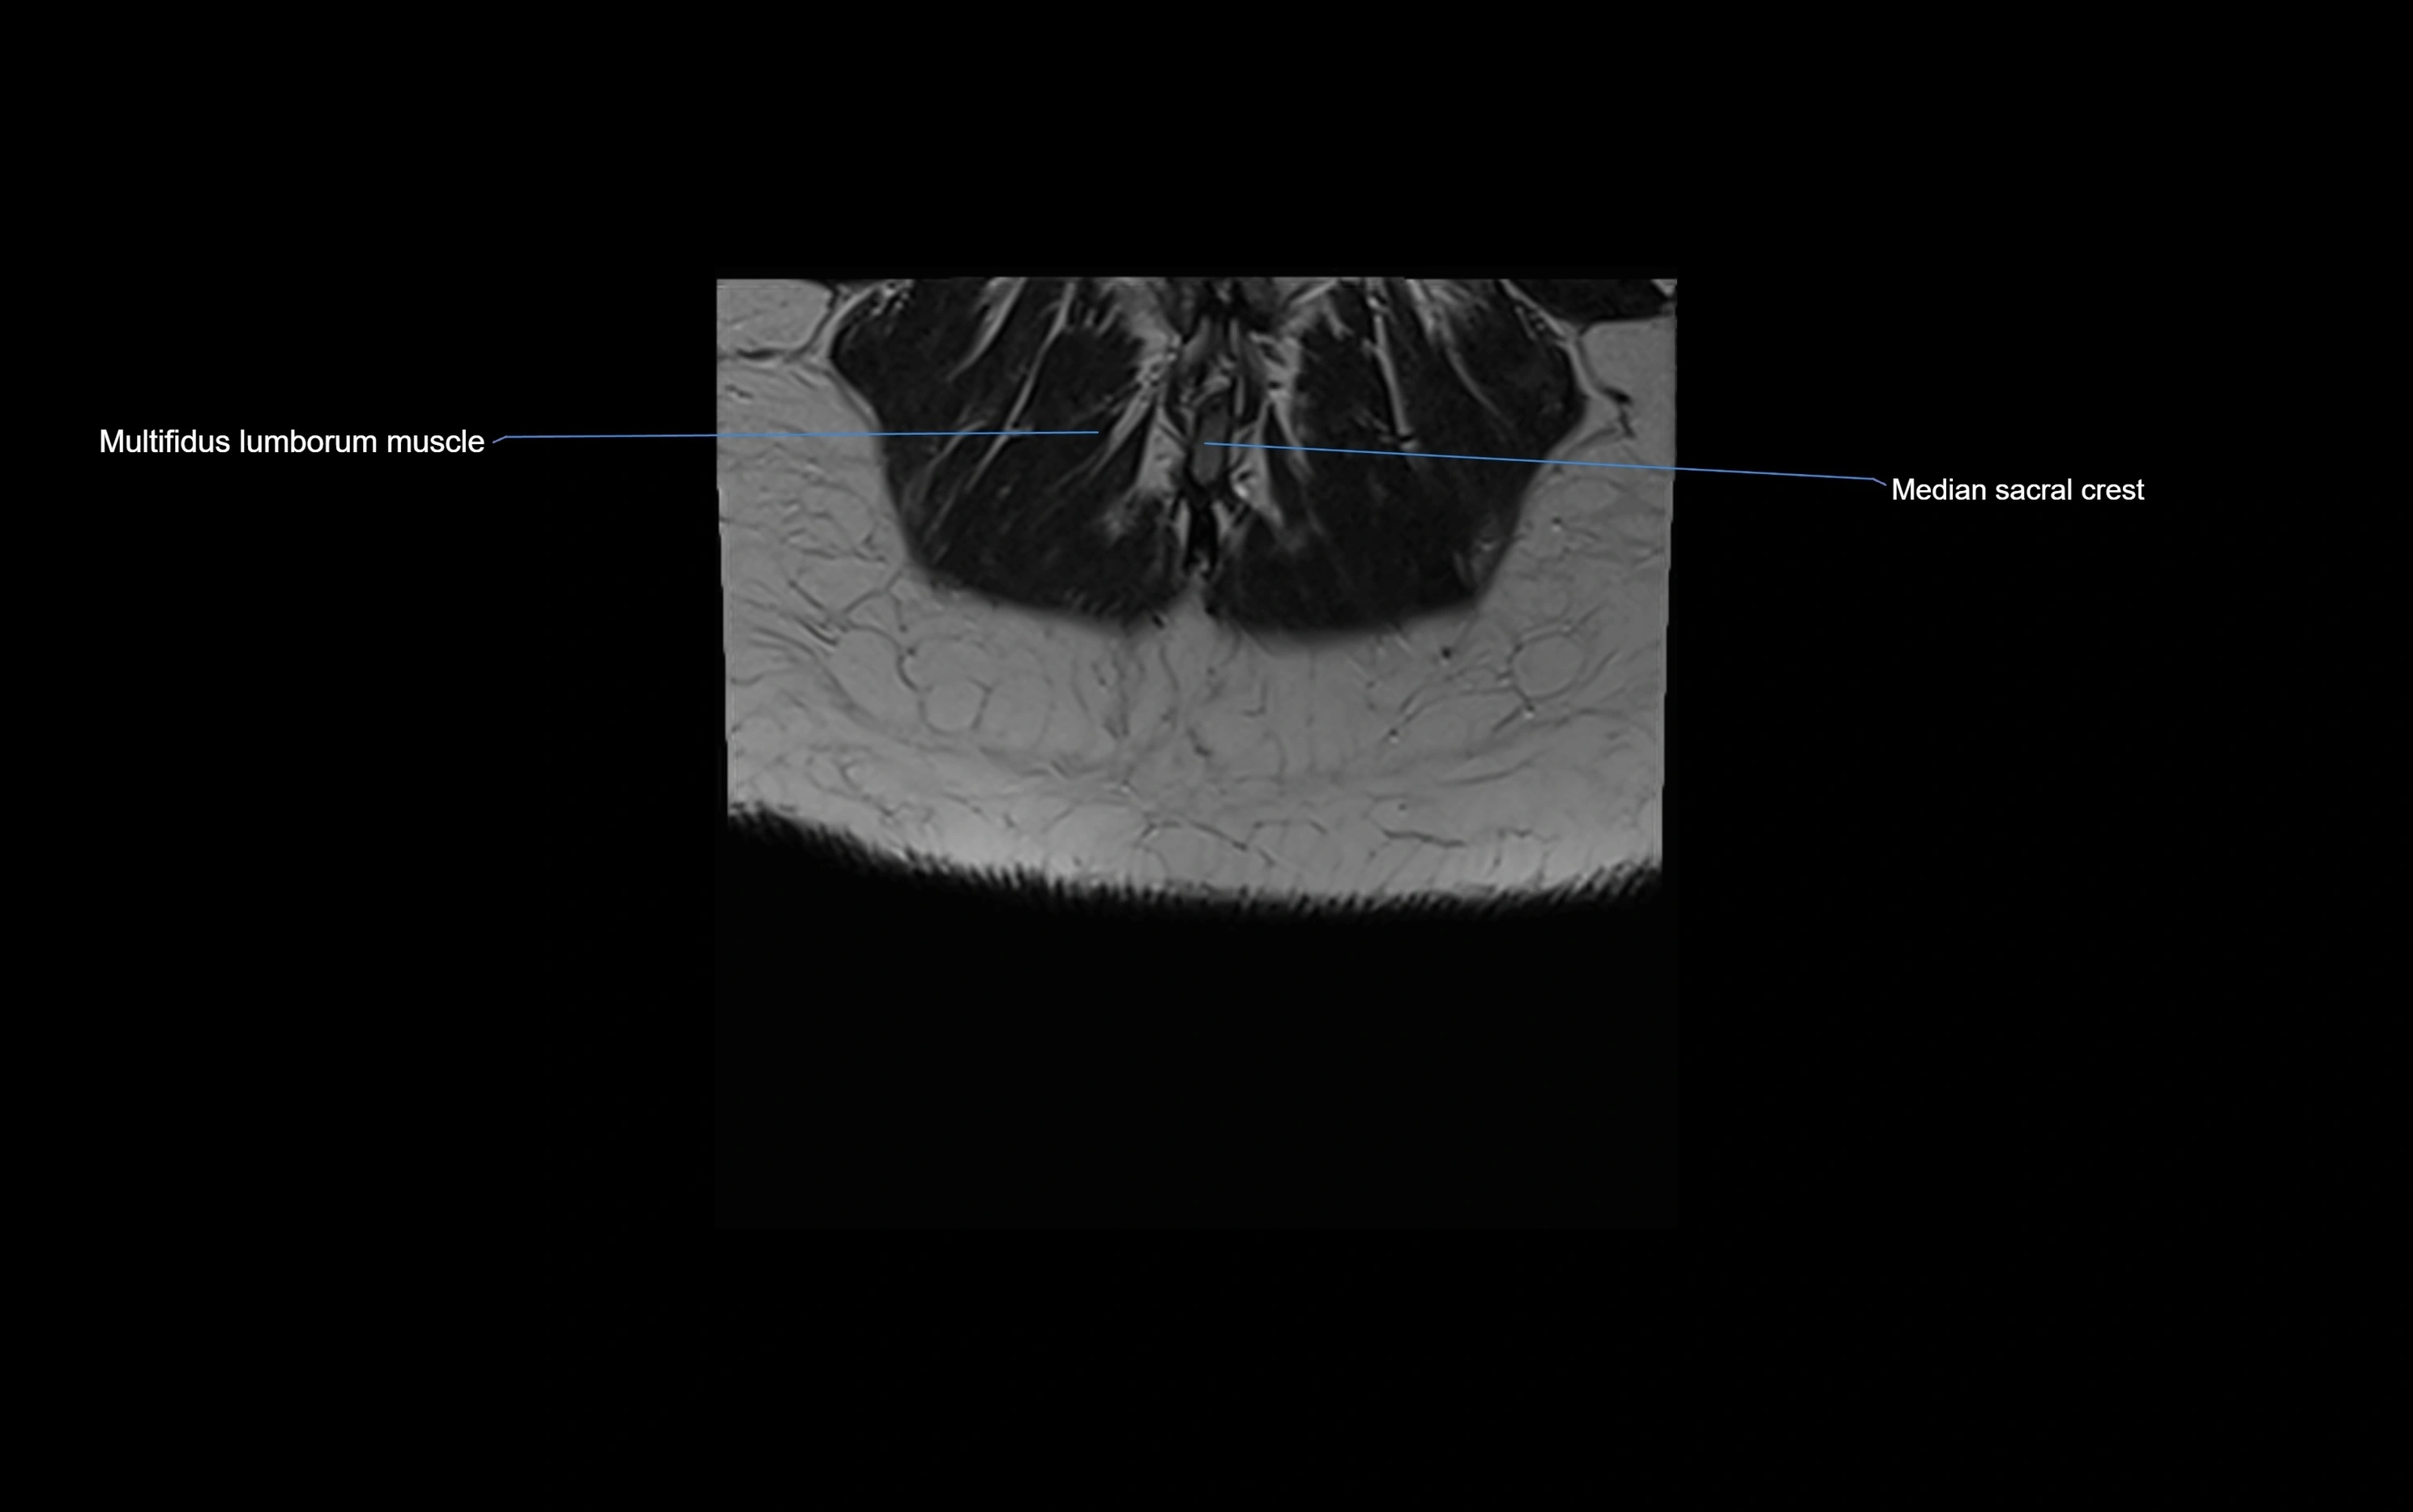

MRI image

image

MRI Appearance

T1-weighted images:

• Cortical bone appears very low signal (dark); marrow shows intermediate signal

• Iliac fossa fat is bright against low-signal cortex

T2-weighted images:

• Cortical bone remains dark

• Marrow signal varies depending on fat content; edema or tumor shows hyperintensity

STIR:

• Suppresses fat, making bone marrow edema, fractures, or infiltrative lesions appear bright

• Excellent for trauma, sacroiliitis, and metastatic evaluation